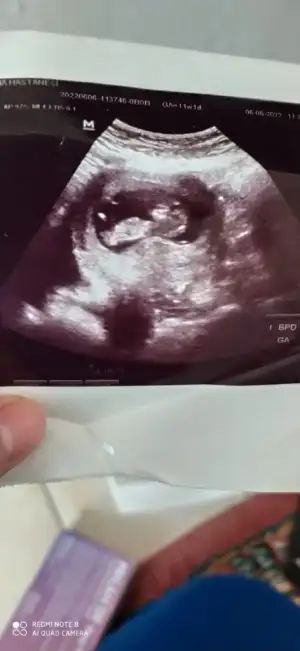

Pasha22 Pasha22 mrb canım daha önce kuzenime tahmin yapmistin doğru çıktı teşekkür ederim bir tane de yengemin cinsiyet tahmini yapar mısın rica etsem 🥰

• IMG-20220622-WA0009.webp

IMG-20220622-WA0009.webp

18,6 KB · Görüntüleme: 69

• IMG-20220622-WA0006.webp

IMG-20220622-WA0006.webp

18,2 KB · Görüntüleme: 61

• IMG-20220622-WA0007.webp

IMG-20220622-WA0007.webp

14,8 KB · Görüntüleme: 71

• IMG-20220622-WA0008.webp

IMG-20220622-WA0008.webp

9,3 KB · Görüntüleme: 64

• IMG-20220622-WA0005.webp

IMG-20220622-WA0005.webp

10,5 KB · Görüntüleme: 66